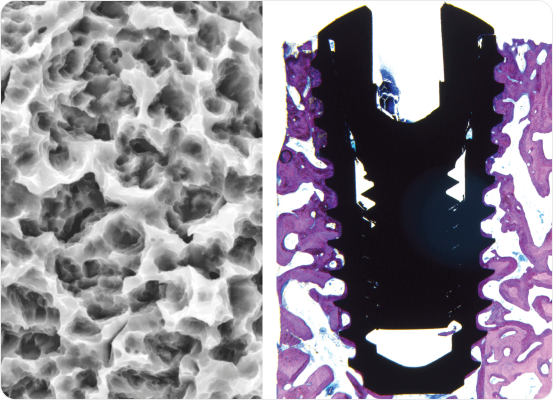

S.L.A. surface treatment (sandblasted and acid-etched) enhances osseointegration and long-term stability.

Sharper, deeper threads with increased pitch are designed to minimize bone trauma, enhance primary stability, and maximize bone-implant contact.

A 3-blade self-tapping design with a flat apical end ensures efficient cutting and placement across all bone types.